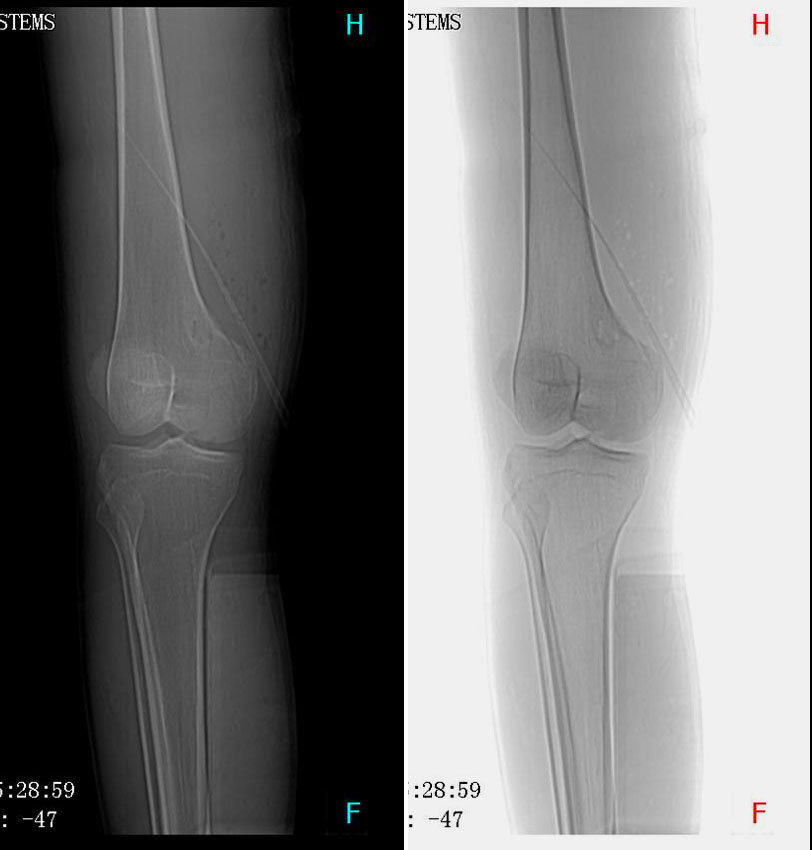

CT50034:男性,24岁。外伤入院

【结果公布】 男性,24岁。 患者因骑摩托车不慎跌倒,左上臂及右大腿受到撞击致疼痛,活动受限15小时入院。

[病理诊断] CT50034:(股骨)骨促结缔组织增生性纤维瘤。

左股骨外侧髁骨折伴纤维性骨皮质缺损

左股骨外侧髁骨折伴纤维性骨皮质缺损。

骨折并纤维性骨皮质缺损或非骨化性纤维瘤。

股骨下端纵型骨折,骨折线触及关节面